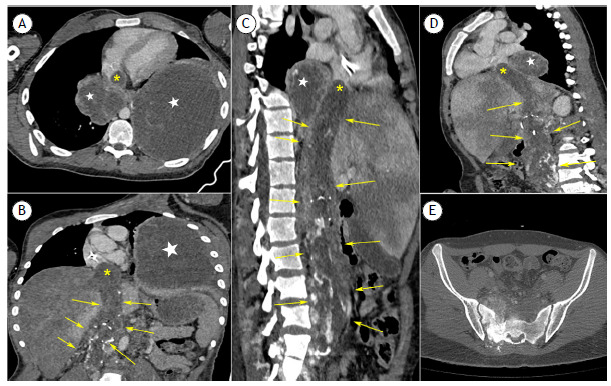

High-grade chondrosarcoma of the sacrum with mediastinal metastases and a tumor thrombus to the inferior vena cava and right atrium.

骶骨高级别软骨肉瘤伴纵隔转移和肿瘤血栓至下腔静脉和右心房。